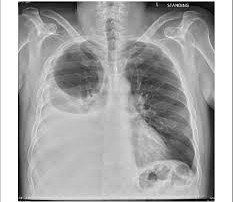

El neumotórax en pediatría representa un desafío clínico que exige una alta sospecha diagnóstica y una intervención precisa. Esta patología, caracterizada por la acumulación de aire en el espacio pleural que provoca el colapso del parénquima pulmonar, suele presentarse bajo tres escenarios críticos. El neumotórax espontáneo primario (nep) es el más común en adolescentes varones de complexión asténica, frecuentemente debido a la ruptura […]